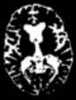

Progressive brain atrophy

Cerebral atrophy is a common feature of many of the diseases that affect the brain. Atrophy of any tissue means a decrement in the size of the cell, which can be due to progressive loss of cytoplasmic proteins. [Source: Wikipedia ]